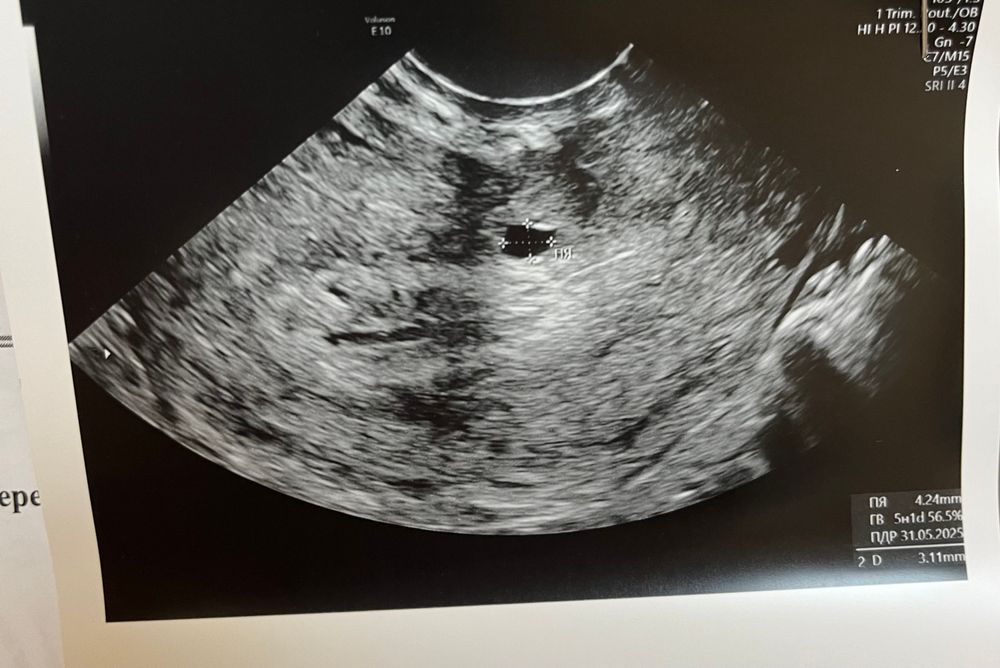

Точно ли это плодное яйцо?

На что ещё похоже кроме плодного яйца??Я уже не знаю что думать,очень много несостыковок 🥺